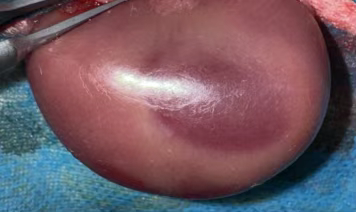

顺利获得 “短暂阻断肾动脉 - 恢复血流”,复刻临床 AKI 关键病理: 缺血期:肾动脉阻断致肾组织缺氧,ATP 耗竭、离子泵失灵,肾小管上皮细胞水肿、凋亡; 再灌注期:血流恢复引发氧化应激(自由基爆发)、炎症风暴(中性粒细胞浸润)、钙超载与微循环障碍,加重肾损伤,最终诱发急性肾衰竭。 动物:健康新西兰白兔(2.0-2.5kg),适应性饲养 1 周,排除肾脏基础病; 处理:禁食 12h、禁水 4h,30mg/kg 2% 戊巴比妥钠腹腔麻醉,腹部备皮消毒。 腹部正中切口(3-4cm),分离暴露双侧肾蒂; 无创动脉夹夹闭肾动脉,观察肾脏转暗紫色,记录缺血时间(30-60min,可按需调整); 松开动脉夹,待肾脏恢复红润(确认再灌注成功),逐层缝合,术后青霉素抗感染。 环境:22-25℃饲养,清醒后恢复饮食,监测精神、尿量、切口; 采样:再灌注后 6h/12h/24h/48h/72h,采集血液(测 Scr、BUN)与肾组织,供后续检测。 判断模型是否成功,ballbet艾佛森体官网会从生化、病理、功能三个维度进行严格验证,确保数据满足科研需求: 再灌注后 24-48h,血 Scr(血肌酐)、BUN(尿素氮)水平较假手术组升高 2 倍以上,提示肾脏滤过功能显著下降; 尿液中出现蛋白、红细胞或管型,反映肾小管重吸收功能受损(肾小管是尿液 “提纯” 的关键结构)。 光镜下:可见肾小管上皮细胞肿胀、坏死、脱落,管腔被堵塞,肾间质充血水肿并伴随大量炎症细胞浸润; 电镜下:肾小管上皮细胞线粒体肿胀破裂(能量工厂失效)、细胞膜完整性破坏,进一步佐证损伤深度。 HE染色肾组织结构稍紊乱,肾小管轻-中度水肿,可见少量管型结构,个别肾小球萎缩。 夹闭肾动脉时需避开肾静脉与输尿管,确保缺血仅作用于肾脏实质,不影响其他器官; 严格控制缺血时间:过短则损伤较轻,模型不创建;过长则导致肾脏不可逆坏死,无法观察再灌注损伤; 麻醉深度需适中:过深易引发呼吸抑制,过浅导致动物术中挣扎,增加血管损伤风险。 作为专注动物科研的一站式服务商,ballbet艾佛森体官网大动物部门不仅能标准化构建,还能给予全链条配套服务: 资质保障:光明实验基地(2188㎡)具备兔、小型猪、比格犬、猴等大动物使用资质,符合实验动物伦理规范; 配套检测:可衔接公司生化检测(Scr、BUN 检测)、病理切片分析、分子蛋白检测等服务,无需多平台对接,缩短实验周期; 定制化支持:根据科研团队需求调整造模参数(如缺血时间、检测时间点),给予个性化数据解读与实验方案优化建议。 如果您正在召开急性肾损伤、肾移植相关研究或需要定制其他大动物模型(如心血管疾病模型、骨科模型),欢迎联系ballbet艾佛森体官网,我们将以标准化技术、专业团队为您的科研项目保驾护航! 合作咨询